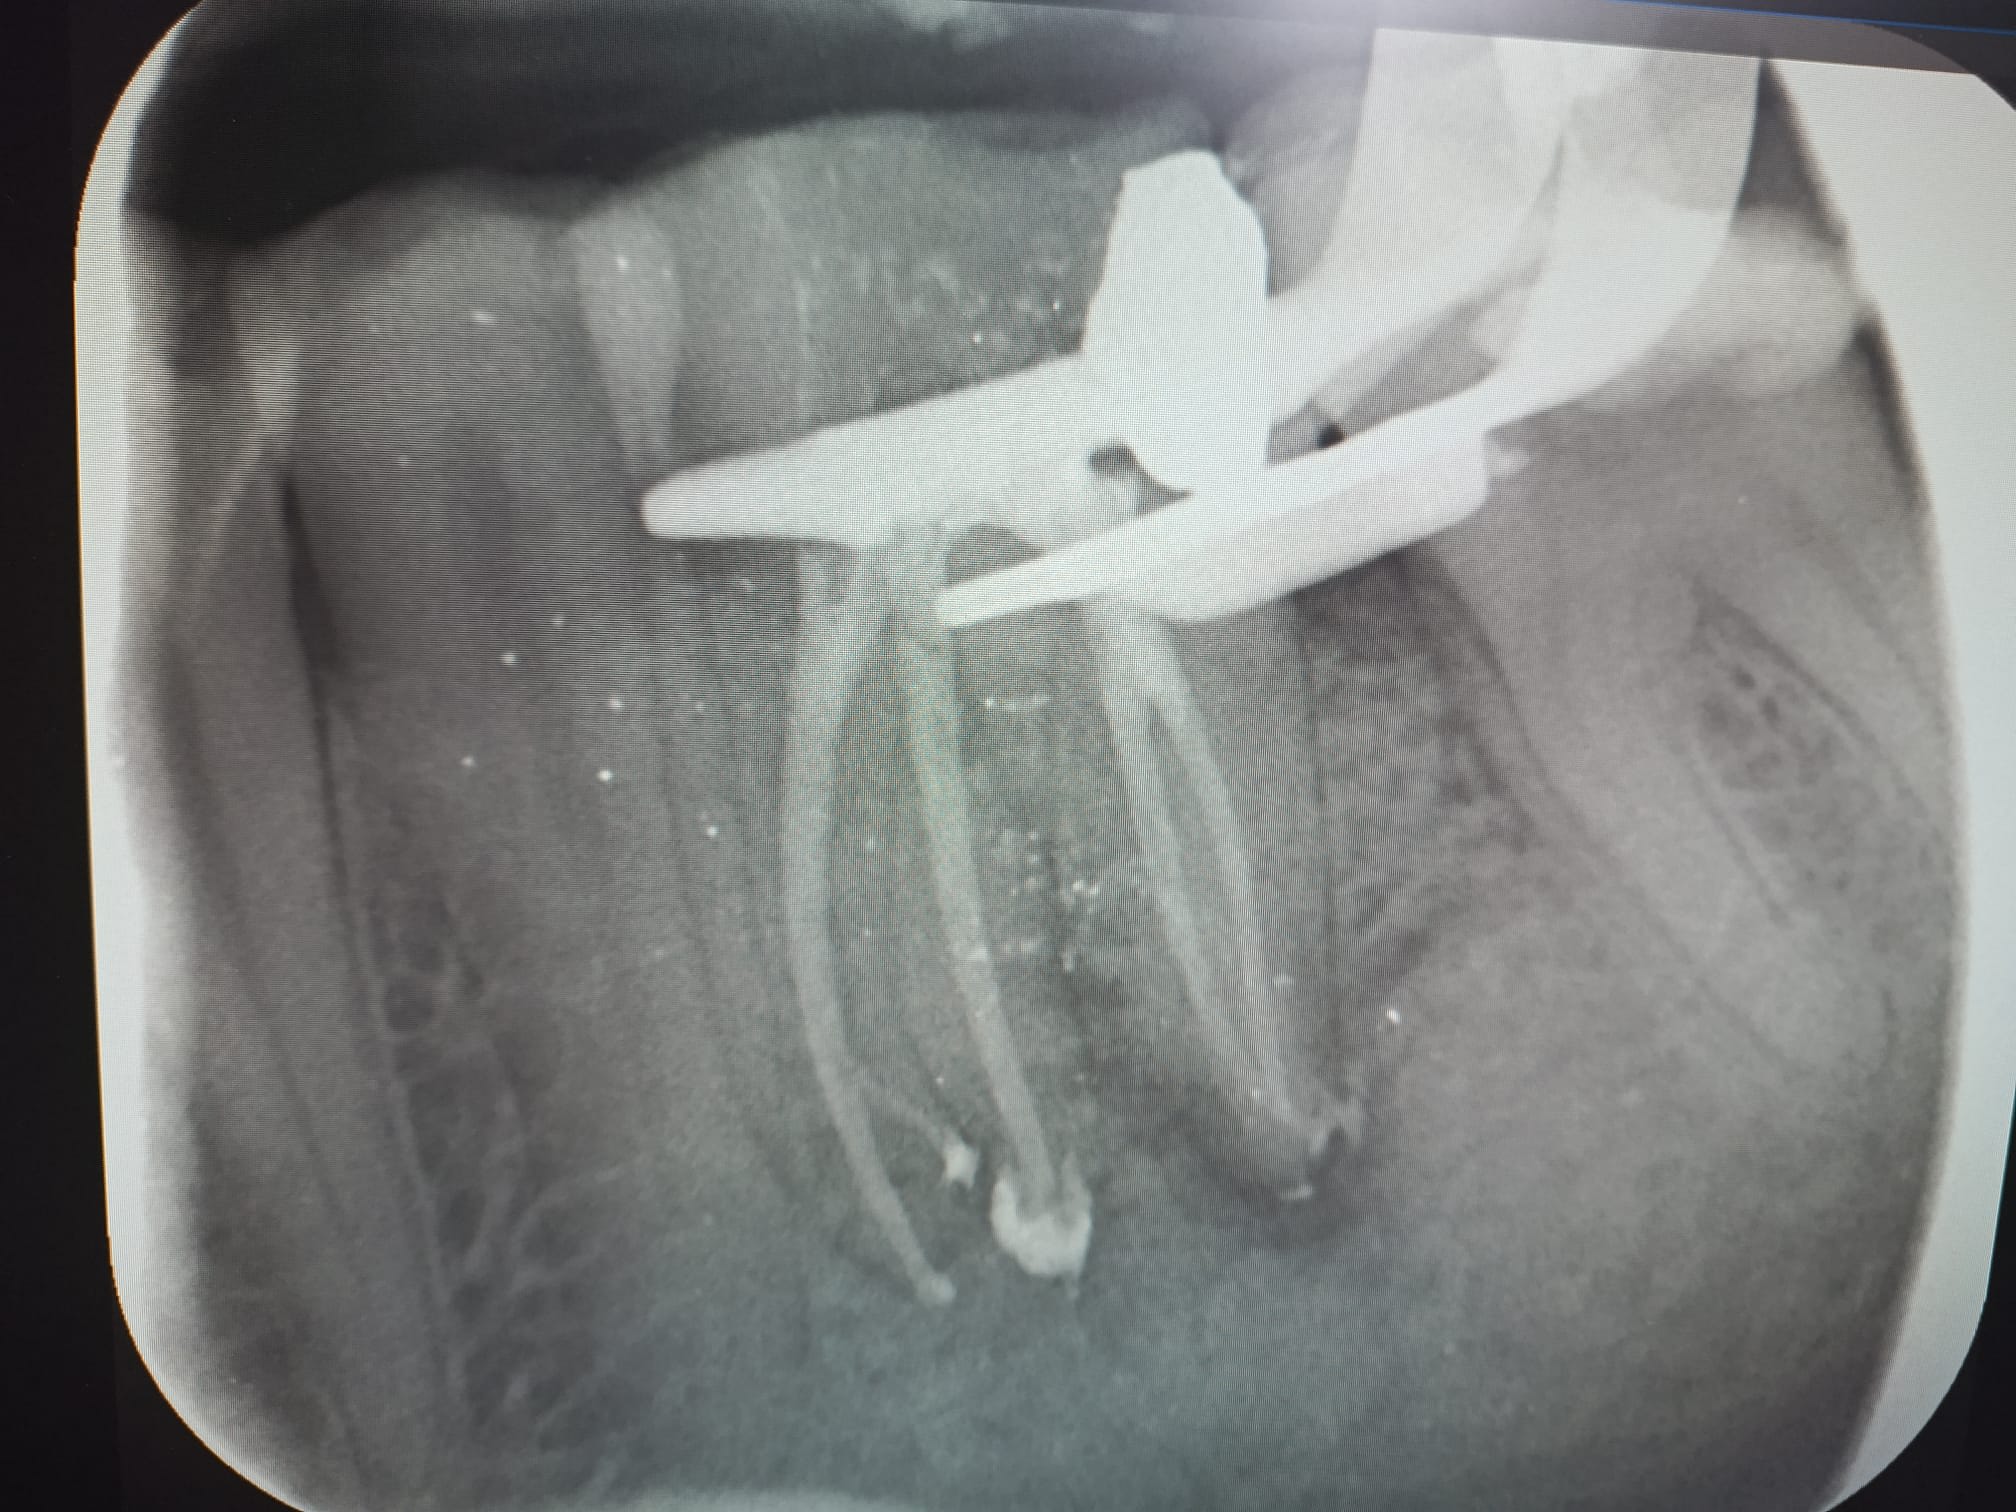

Par contre sur ce cas au social le dentiste conseil n'a accepté que trois canaux.